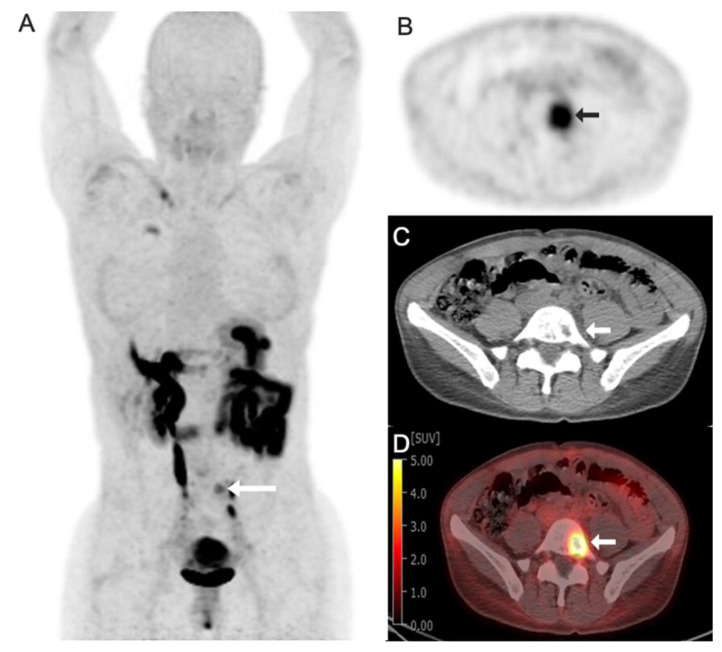

Targeted radioligand therapy (RLT) is an emerging field in anticancer therapeutics with great potential across tumor types and stages of disease. While much progress has focused on agents targeting somatostatin receptors and prostate-specific membrane antigen (PSMA), the same advanced radioconjugation methods and molecular targeting have spurred the development of numerous theranostic combinations for other targets. A number of the most promising agents have progressed to clinical trials and are poised to change the landscape of positron emission tomography (PET) imaging. Here, we present recent data on some of the most important emerging molecular targeted agents with their exemplar clinical images, including agents targeting fibroblast activation protein (FAP), hypoxia markers, gastrin-releasing peptide receptors (GRPrs), and integrins. These radiopharmaceuticals share the promising characteristic of being able to image multiple types of cancer. Early clinical trials have already demonstrated superiority to 18F-fluorodeoxyglucose (18F-FDG) for some, suggesting the potential to supplant this longstanding PET radiotracer. Here, we provide a primer for practicing radiologists, particularly nuclear medicine clinicians, to understand novel PET imaging agents and their clinical applications, as well as the availability of companion targeted radiotherapeutics, the status of their regulatory approval, the potential challenges associated with their use, and the future opportunities and perspectives.